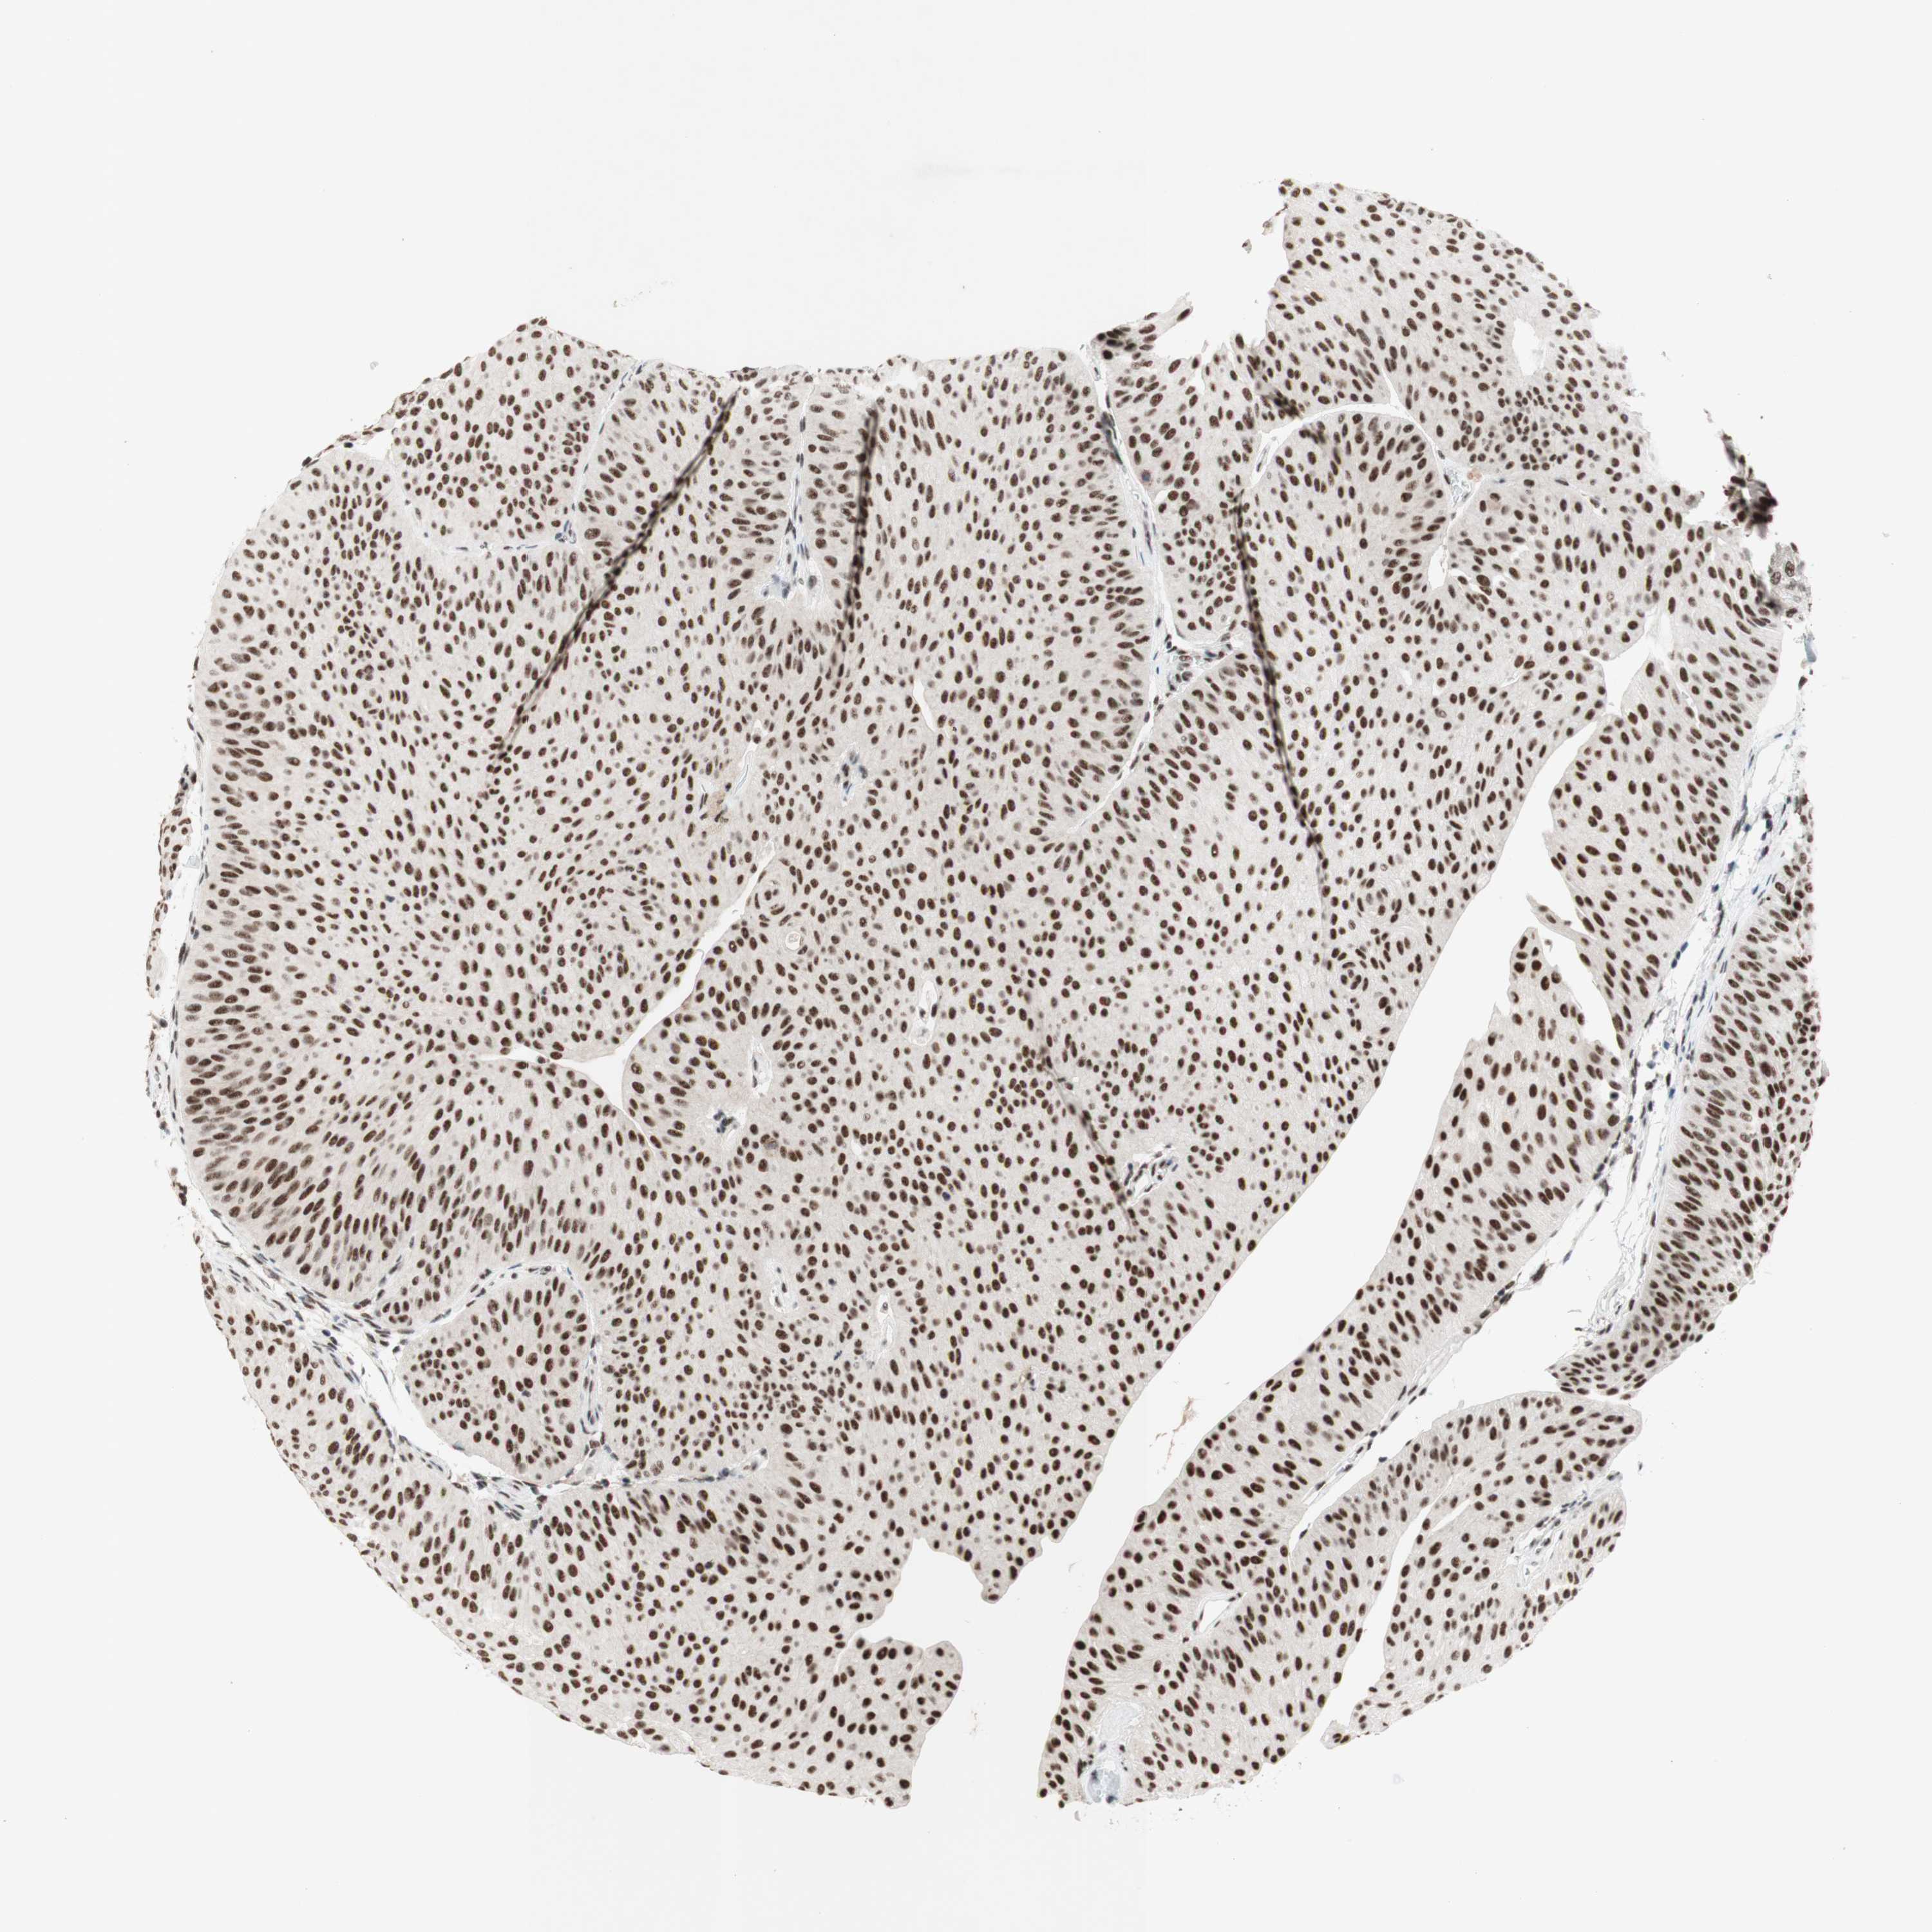

UROTHELIAL CANCER - Protein expressioni

A mouse-over function shows sample information and annotation data. Click on an image to view it in a full screen mode. Samples can be filtered based on level of antibody staining by selecting one or several of the following categories: high, medium, low and not detected. The assay and annotation is described here.

Note that samples used for immunohistochemistry by the Human Protein Atlas do not correspond to samples in the TCGA dataset.

Antibody stainingi

Antibody staining in the annotated cell types in the current human tissue is reported as not detected, low, medium, or high, based on conventional immunohistochemistry profiling in selected tissues. This score is based on the combination of the staining intensity and fraction of stained cells.

Each image is clickable and will lead to virtual microscopy that enables deeper exploration of all samples and also displays staining intensity scores, fraction scores and subcellular localization as well as patient and tissue information for each sample.

Antibody HPA038051

Antibody HPA059070

Antibody CAB012448

Staining

High

Medium

Low

Not detected

Intensity

Strong

Moderate

Weak

Negative

Quantity

>75%

75%-25%

<25%

None

Location

Nuclear

Cytoplasmic/membranous

Cytoplasmic/membranous,nuclear

Urothelial carcinoma, High grade

Urothelial carcinoma, Low grade

Urothelial carcinoma, NOS